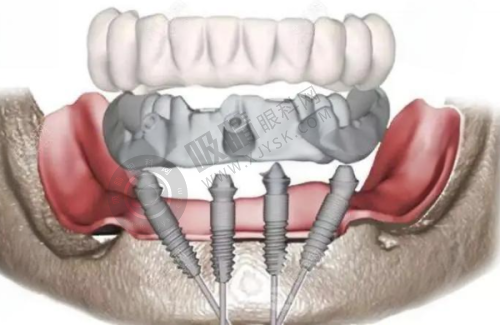

陕西省人民医院口腔科可开展全口数字化种植、ONLY 植骨术、骨劈开术、GBR 手术、即刻种植、上颌窦外提升等高难度的种植技术。

西安交通大学医学校第一附属医院口腔科引入机器人种植(5 分钟/颗)、3D 导板设计,减少人力与耗材浪费;提供3D 数字化模拟矫正方案,提前预览牙齿移动轨迹。

西安交大口腔正畸科提供3D 数字化方案设计,修复科引进德国即刻种植技术